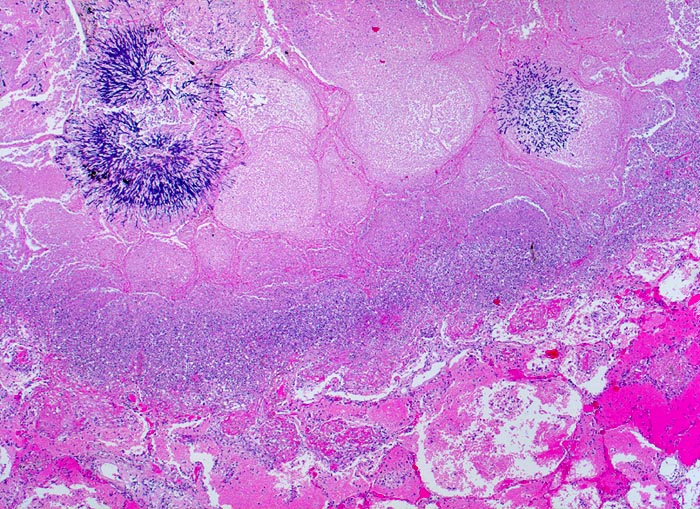

Einleitung

Aspergillen gehören in die Gruppe der Schimmelpilze und wachsen ubiquitär auf organischen Stoffen. Der Erreger ist charakterisiert durch echte septierte Hyphen von 3 bis 6 Mikrometer Durchmesser. Die Hyphen verzweigen sich in einem Winkel von 45 Grad. Selten sind auch die (> 10851) (> 10849) Fruchtköpfe (Conidiophoren) nachweisbar. Aspergillusinfekte manifestieren sich je nach Resistenzlage als Aspergillom, invasive Aspergillose oder allergische Aspergillose. Der Nachweis von Aspergillus beweist noch nicht eine klinisch relevante Infektion.